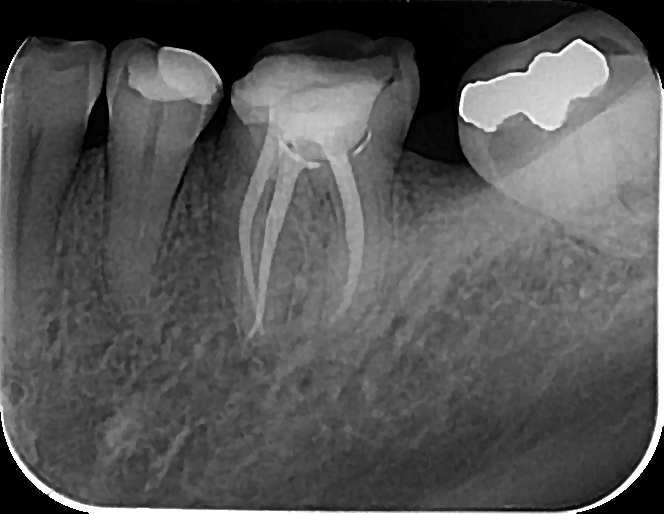

Slika 3. Blue R3 (Fanta Dental, Shanghai, China)

Ako sumiramo, recipročan pokret nam donosi sigurnu preparaciju uz blag apikalni pritisak pri čemu se imitira pokret balansiranih sila. Može se izvući zaključak da je zbog smanjenog cikličnog zamora i torzionog stresa produžen vek trajanja instrumenata (mada su jasna uputstva proizvođača o broju korišćenja). Potreban je jedan instrument za celokupnu obradu kanala (Slika 3), pa je vreme preparacije kraće, a primena jednostavna. Ipak, u slučaju kompleksne kanalne anatomije, često nismo u mogućnosti da jednim instrumentom završimo celokupnu preparaciju kanala. Sistemi koji koriste pokret kontinuirane rotacije 360 ° su pak mnogo brojniji i raznovrsniji na tržištu. Zbog većeg broja sekvenci, i vreme preparacije je duže, pa se godinama radilo na smanjenju broja instrumenata. Danas imamo dostupne sisteme od jednog instrumenta i za pokret kontinuirane rotacije, koji su izuzetno efikasni (Slika 4). Pokretom kontinuirane rotacije se postiže bolje uklanjanje debrija i manja je mogućnost za nastanak mikropukotina u dentinu. Problem cikličnog zamora i stresa je rešen kontrolom obrtnog momenta. Najvažnije, efikasnost rotirajućih instrumenata koji se aktiviraju ražličitim pokretima je ista. Na sreću, danas se sve više proizvođača odlučuje za endo motore koji nam nude mogućnost izbora, jer podržavaju obe kretnje. Na nama je da se u zavisnosti od postavljene dijagnoze, kompleksnosti kanalnog sistema, a prevashodno našeg znanja i iskustva opredelimo za određeni sistem i način aktivacije.